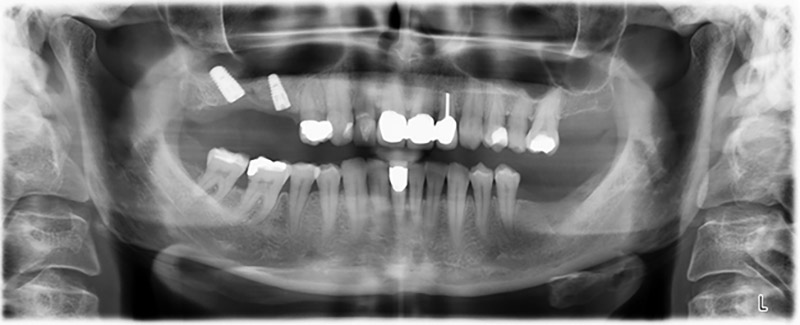

Шест месеца след екстракцията на зъби 16 и 14 се извършва преглед с дигитален томограф (DVT, Planmeca), с цел планиране и намаляване на възможните рискове. Ясно се вижда, че костта не се е регенерирала до желания обем (Фиг. 2 до 7).

Снимки 2 до 7: DVT със силно намален хоризонтален костен обем.

Синус лифтът е задължителен и за двете зони 16 и 14, за да се гарантира фиксирано възстановяване, базирано на поне два импланта. Сравнително голяма костна аугментация е необходима, тъй като обемът на остатъчната кост е изключително малък в този случай. Процедурите с голяма костна аугментация са инвазивни и се свързват с висока заболеваемост на пациентите, както и отнемат много време и са скъпи. По-трудно е да се предвидят резултатите от лечението и рискът от неуспех е увеличен. Пациентката е информирана за големия риск и е предложено алтернативно решение, което тя последователно отхвърля.

За да ограничим аугментацията до зона 14, след консултация с пациентката, е планирано поставяне на имплант в зона 16, наклонен по посока на челюстта (Фиг. 8).